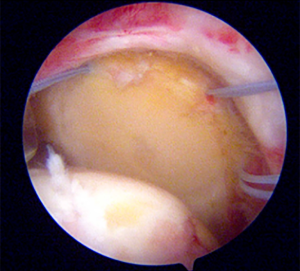

Diagnostic arthroscopy

For SCR, a direct lateral portal was used as the main viewing portal in a standard beach chair position. A standard diagnostic arthroscopy was performed to confirm the status of the articular cartilage and the subscapularis integrity. The subscapularis integrity is important as the presence of it will associated with the clinical outcomes and complication rates following SCR (47). More importantly, detailed assessment of the rotator cuff tears should be performed after meticulous removal of the degenerative subacromial bursal tissue and articular release (Figure 2). To assess the repairability of the tendon, a retriever was usually used to grasp the tendon edge and reduce it to the footprint through an anterolateral portal. The distance between the expected anterior glenoid anchor and the expected anterior medial row humeral anchor was measured using a probe (mediolateral graft length) (23). The distance between the expected anterior to the posterior glenoid and medial humeral anchor was also measured (anteroposterior graft length). A radiofrequency ablation device was used to mark the location for the anchor. The graft harvesting and preparation are performed once the tear has been decided to be irreducible.